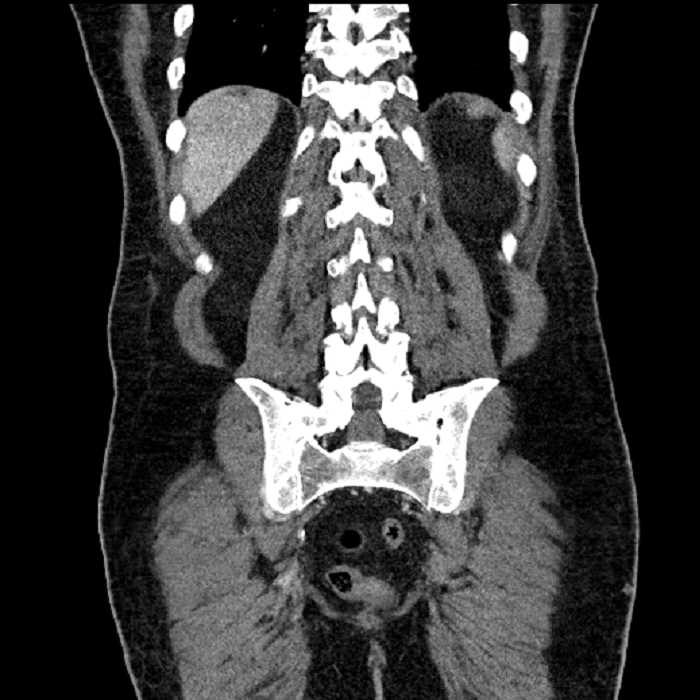

Age: 63

Sex: Male

Indication: Abdominal pain

• Large fluid density structure in hepatic segments 7 and 8 measuring 10 x 7 x 7 cm with internal septation and circumferential ill-defined low density compatible with edema

• Peripherally enhancing subcapsular collections along the anterior margin of the left hepatic lobe measuring 3 x 1 cm and 2 x 1 cm

• Clearly marginated fluid density structure in segment 7 and several other scattered tiny hypodensities, which likely represent cysts

Acute sigmoid diverticulitis complicated by a small contained perforation and a large abscess in the right hepatic lobe. Additional small subcapsular abscesses along the anterior margin of the left hepatic lobe.

Additionally, loss of the normal fat plane between the peridiverticular collection and adjacent thickened loops of small bowel raises the potential for an enterocolonic fistula.